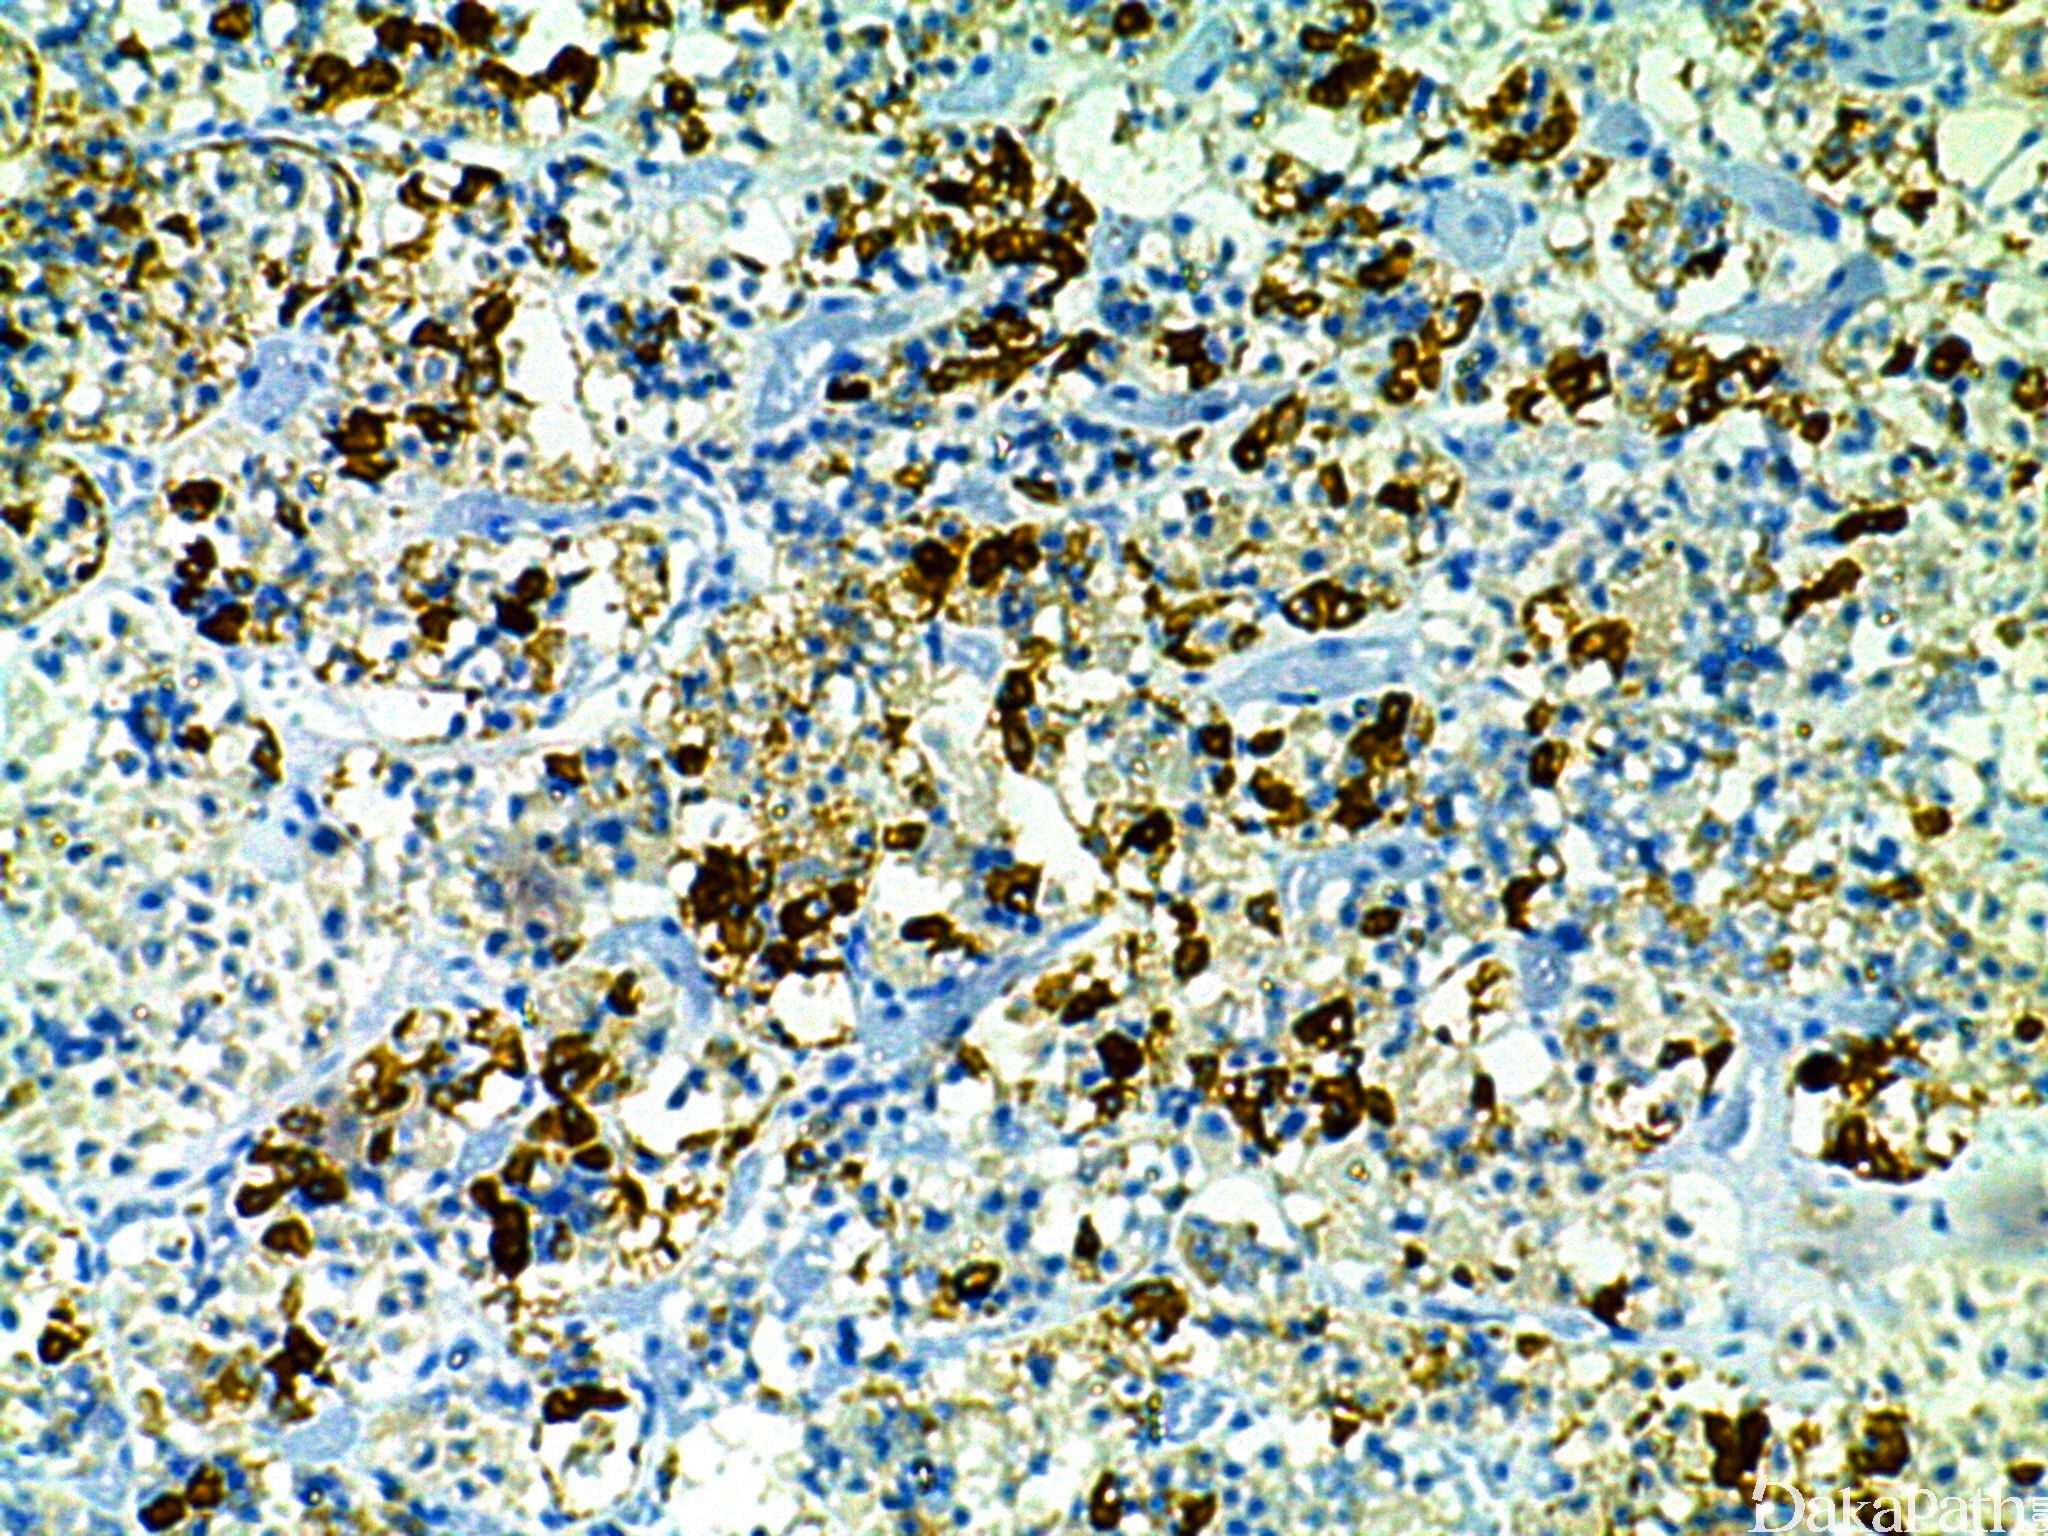

几乎全部阳性(≥95%的病例阳性): 垂体腺瘤,分泌促甲状腺激素

几乎全部阴性(<5%的病例阳性): 垂体腺瘤,裸细胞、脑垂体梭形细胞嗜酸细胞瘤